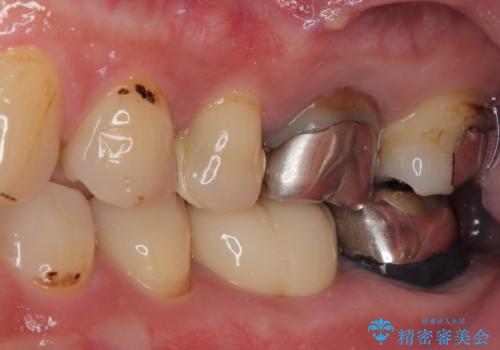

- 下顎大臼歯が噛めないほどの痛みを感じるとのことで来院された患者様です。

レントゲン写真などで診査を行ったところ、不適合な詰め物の周りから炎症が波及し、神経組織が壊死していると診断されました。

まずは根管治療を行い、症状が消退したことを確認してオールセラミッククラウンにて補綴治療を行うこととしました。